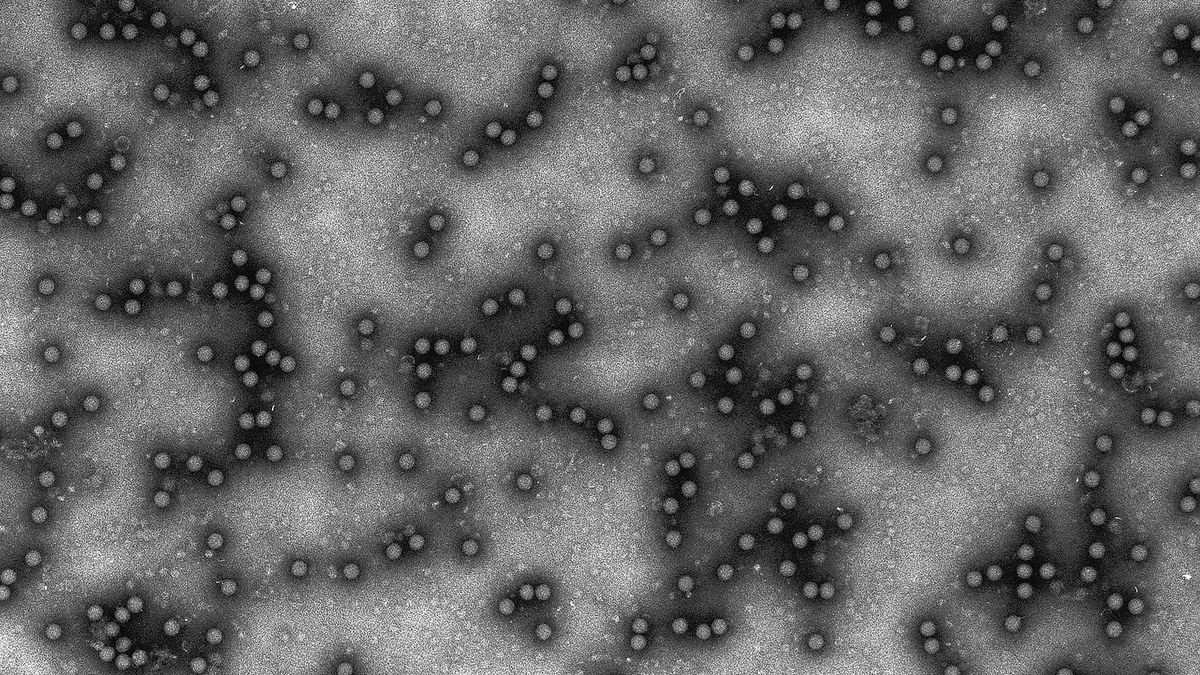

Verursacht wird die Krankheit durch ein Virus. Anstecken können sich vor allem Klauentiere wie Rinder und Schweine, Schafe und Ziegen. Die betroffenen Tiere haben hohes Fieber, starke Schmerzen und lahmen, auĂerdem bilden sich an Zunge und Lippen, an Klauen und Zitzen viele BlĂ€schen.Â

Von der Infektion bis zu den ersten Symptomen dauert es nur zwei bis sieben Tage, deswegen kann sich die Seuche schnell ausbreiten. Tödlich verlĂ€uft sie nur selten, allerdings ist die Sterblichkeit bei Jungtieren höher. Tiere, die genesen sind, bleiben oft geschwĂ€cht. KĂŒhe geben oft kaum noch Milch. Auch können diese Tiere das Virus noch lange Zeit ausscheiden.

Das Virus kann monate- oder gar jahrelang infektiös bleiben, auch wenn es im Erdboden ist oder eingetrocknet. Es kann direkt von Tier zu Tier weitergegeben werden, etwa ĂŒber den Atem, aber es kann sich auch ĂŒber die RĂ€der von Fahrzeugen oder an Schuhsohlen und Kleidung verbreiten. In Deutschland wurde das Virus vor dem aktuellen Fall zuletzt vor mehr als 35 Jahren nachgewiesen. Auch in der ĂŒbrigen EU gab es zuvor seit Jahren keinen bestĂ€tigten Fall.